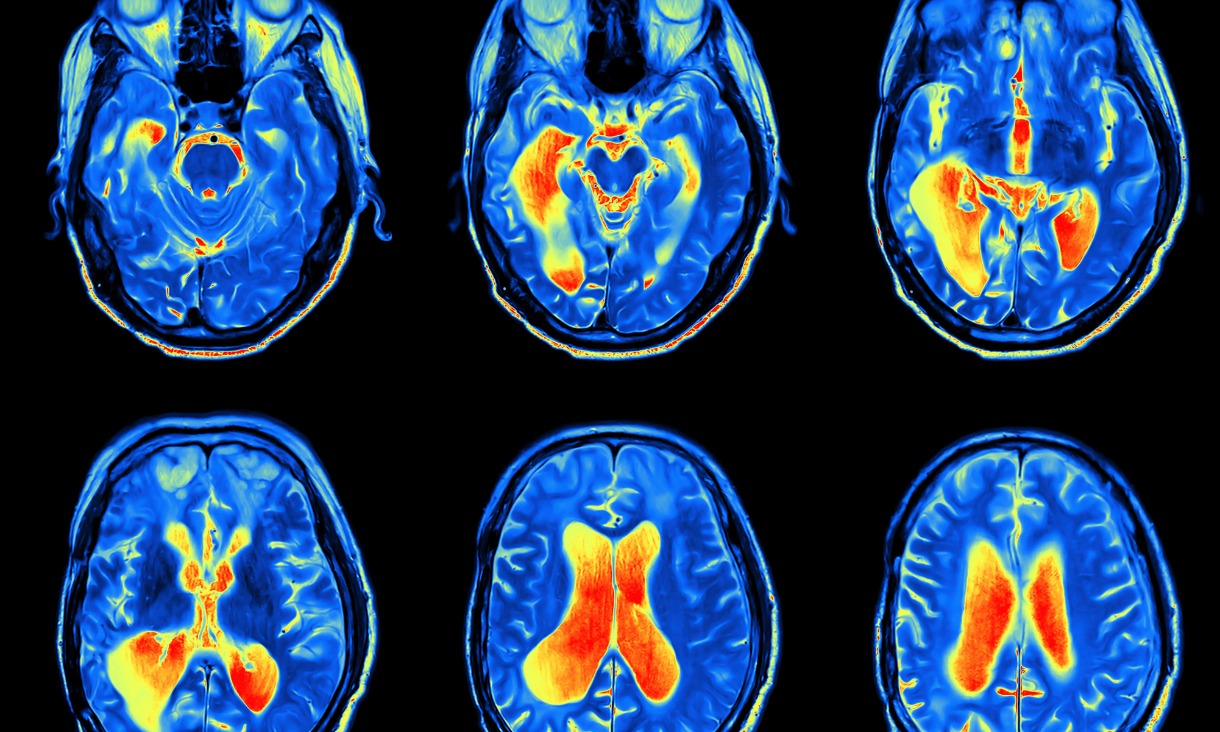

MRI scans of brainsBiofabrication focuses on making structures to restore, replace and regenerate anything from bones and muscles to brain.